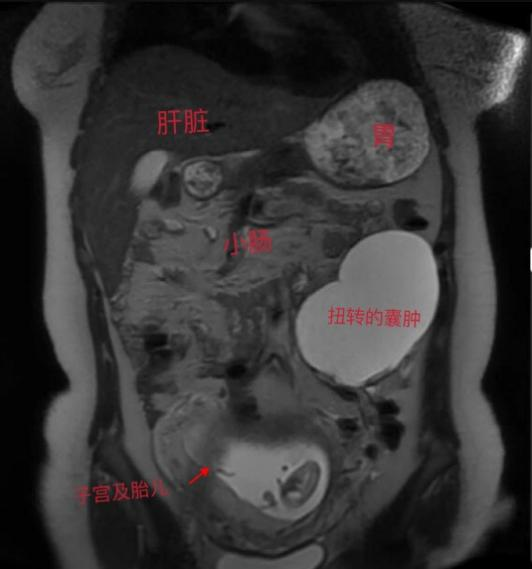

张女士已怀孕4个月,突发下腹疼痛难忍,行B超检查发现怀孕增大的子宫前方有一大约8厘米的卵巢囊肿发生扭转,通常这种情况如不立即手术张女士这一侧的卵巢将会因缺血而坏死需要被切除,妇科接诊后及时给患者施行了单孔腹腔镜囊肿剥除手术,术后张女士宫内胎儿情况良好,腹壁几乎看不见任何伤口,平安顺利出院。